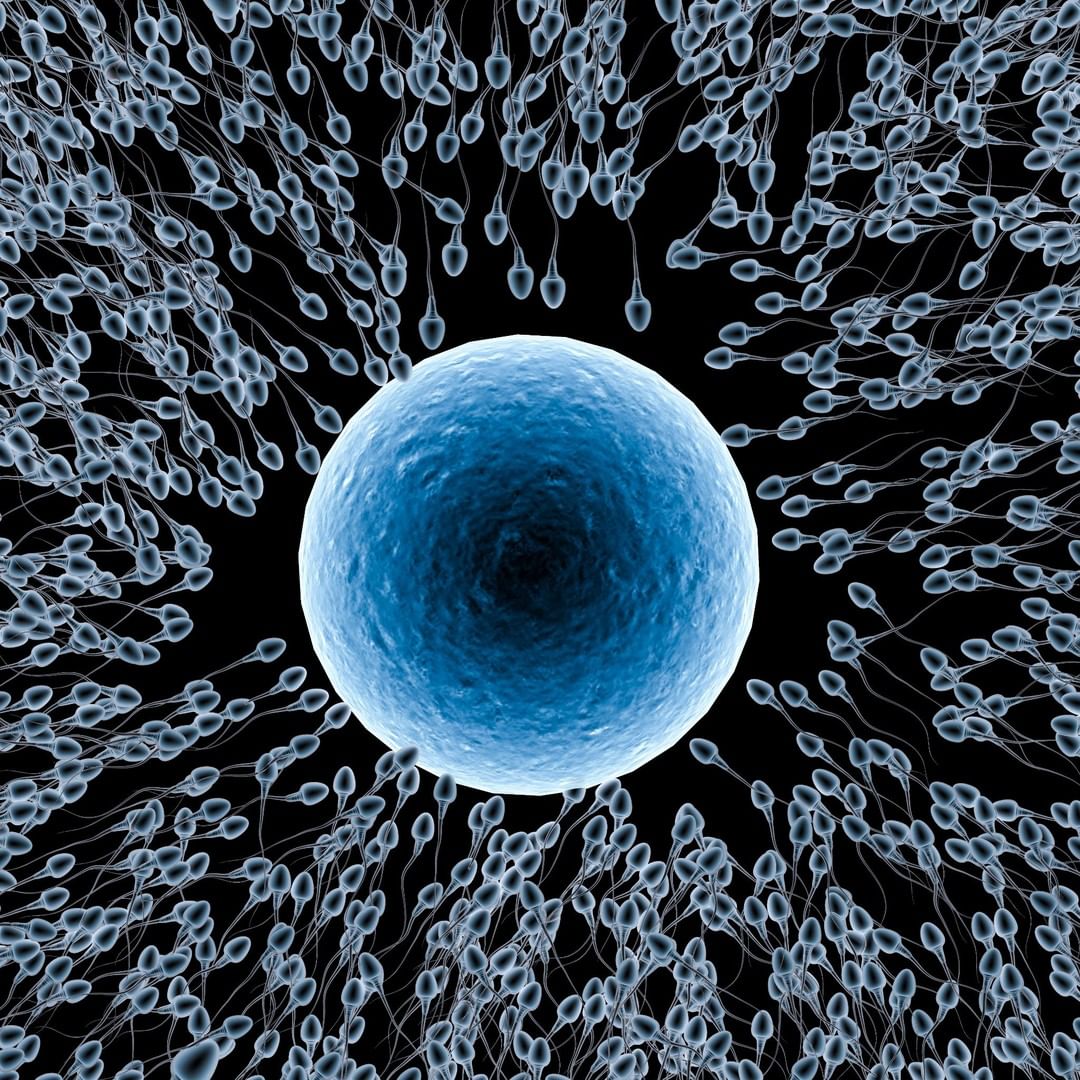

Un óvulo antes de la fecundación, rodeado de espermatozoides